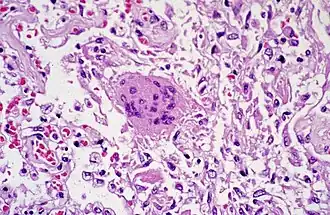

Патологическая анатомия

Обнаруживаются диффузное повреждение лёгочных альвеол, десквамация пневмоцитов, образования гиалиновых мембран и воспалительные инфильтраты[21].